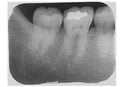

神経の治療など限定された部位を診る場合は小さな

デンタルX線写真